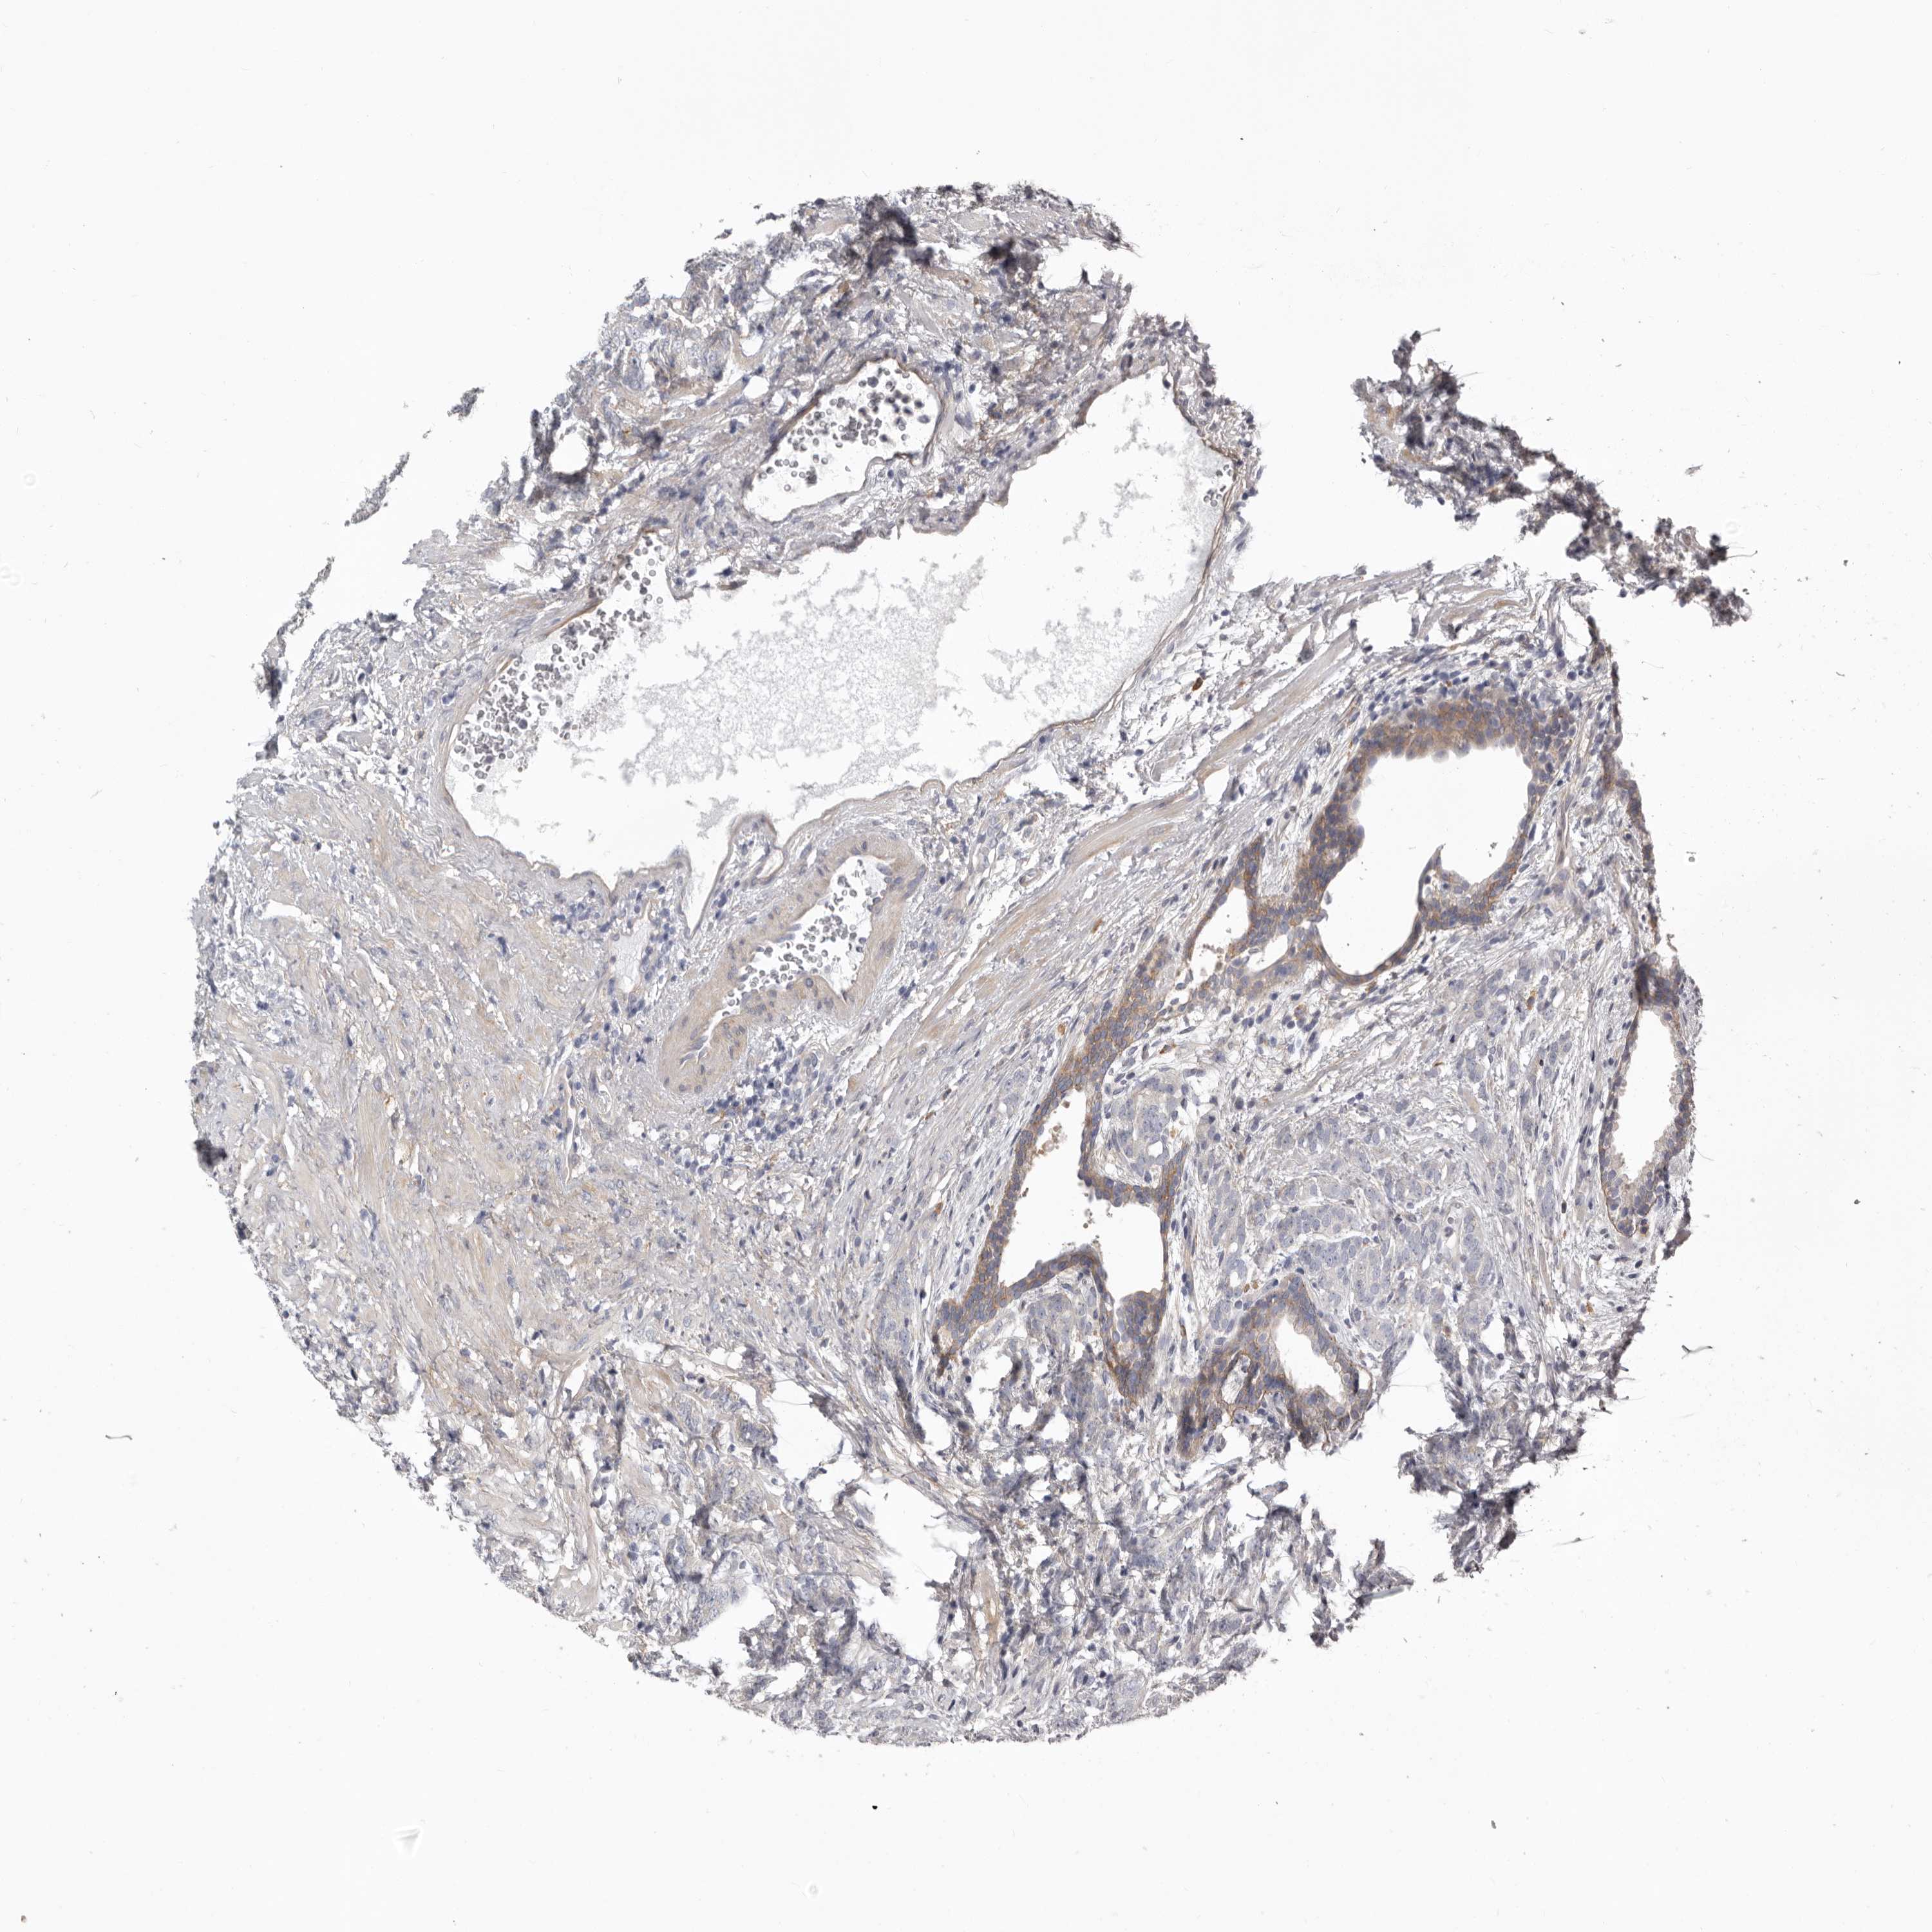

PROSTATE CANCER - Protein expressioni

A mouse-over function shows sample information and annotation data. Click on an image to view it in a full screen mode. Samples can be filtered based on level of antibody staining by selecting one or several of the following categories: high, medium, low and not detected. The assay and annotation is described here.

Antibody stainingi

Antibody staining in the annotated cell types in the current human tissue is reported as not detected, low, medium, or high, based on conventional immunohistochemistry profiling in selected tissues. This score is based on the combination of the staining intensity and fraction of stained cells.

Each image is clickable and will lead to virtual microscopy that enables deeper exploration of all samples and also displays staining intensity scores, fraction scores and subcellular localization as well as patient and tissue information for each sample.

Antibody HPA028448

Antibody HPA028696

Staining

High

Medium

Low

Not detected

Intensity

Strong

Moderate

Weak

Negative

Quantity

>75%

75%-25%

<25%

None

Location

Nuclear

Cytoplasmic/membranous

Cytoplasmic/membranous,nuclear

Adenocarcinoma, High grade

Adenocarcinoma, Low grade

Adenocarcinoma, Medium grade